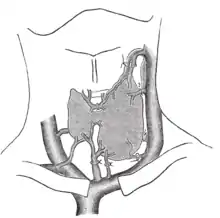

Vascularisation

La thyroïde est un organe richement vascularisé. En effet on retrouve :

- deux artères principales :

- artère thyroïdienne supérieure, première branche de l'artère carotide externe ; elle se divise en 3 branches (latérale, médiale et postérieure) une fois la glande atteinte,

- artère thyroïdienne inférieure, naissant du tronc thyro-cervical, branche collatérale de l'artère subclavière. Se divise également en trois branches (latérale, médiale et postérieure) dans la thyroïde.

Dans de très rares cas il est possible qu'une 3e artère vienne vasculariser la thyroïde dans sa portion basse appelée artère de Neubauer qui est une branche de la crosse de l'aorte. Les deux artères principales de la thyroïde sont anastomosées ; l'ATS droite avec l'ATS gauche et l'ATI droite, et l'ATI droite avec l'ATS droite et l'ATI gauche. Il existe néanmoins d'autres artères, moins volumineuses, inconstantes, naissant directement de l'arc aortique. Par exemple l'artère thyroïdea ima vascularisant la partie isthmique. Celle-ci est présente chez environ 5 à 10 pour cent des sujets et peut provoquer une hémorragie en cas de trachéotomie.

- Trois veines principales :

- veine thyroïdienne supérieure, résultant de la confluence de trois veines dans la glande, et formant avec les veines linguale et faciale le tronc thyro-lingo-facial qui se jette dans la veine jugulaire interne ;

- veine thyroïdienne moyenne, réunion de plusieurs branches pas très volumineuses se jetant dans la veine jugulaire interne ;

- veine thyroïdienne inférieure, formée par la confluence de trois veines dans la glande et se jetant dans le tronc veineux brachio-céphalique.

De même que pour les artères, certaines veines accessoires vascularisant préférentiellement l'isthme vont rejoindre les troncs veineux brachio-céphaliques droit et gauche.